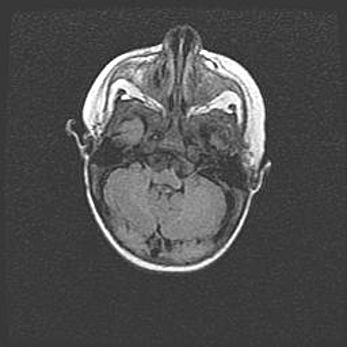

Мальформация Денди-Уокера. Киста задней черепной ямки.

Агенезия мозолистого тела.

Возраст: 2,5 месяца

Вес: 2420 г

Пол: женский

Окружность головы: 37 см

Срок гестации: 32 недели

Мальформация Денди—Уокера — редкий вид патологии ЦНС, представляющий собой врожденный порок развития каудального отдела ствола и червя мозжечка, ведущий к неполному раскрытию срединной (Мажанди) и латеральных (Лушка) апертур IV желудочка мозга. Для этогно синдрома характерна триада симптомов: гипотрофия червя мозжечка и/или полушарий мозжечка, кисты задней черепной ямки, гидроцефалия различной степени. В 70% случаев порок сочетается и с другими аномалиями головного мозга, в частности с агенезией мозолистого тела.